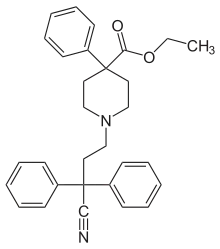

The first fully synthetic opioid was meperidine (later demerol), found serendipitously by German chemist Otto Eisleb (or Eislib) at IG Farben in 1932.[228] Meperidine was the first opiate to have a structure unrelated to morphine, but with opiate-like properties.[199] Its analgesic effects were discovered by Otto Schaumann in 1939.[228] Gustav Ehrhart and Max Bockmühl, also at IG Farben, built on the work of Eisleb and Schaumann. They developed "Hoechst 10820" (later methadone) around 1937.[230] In 1959 the Belgian physician Paul Janssen developed fentanyl, a synthetic drug with 30 to 50 times the potency of heroin.[211][231] Nearly 150 synthetic opioids are now known.[228]